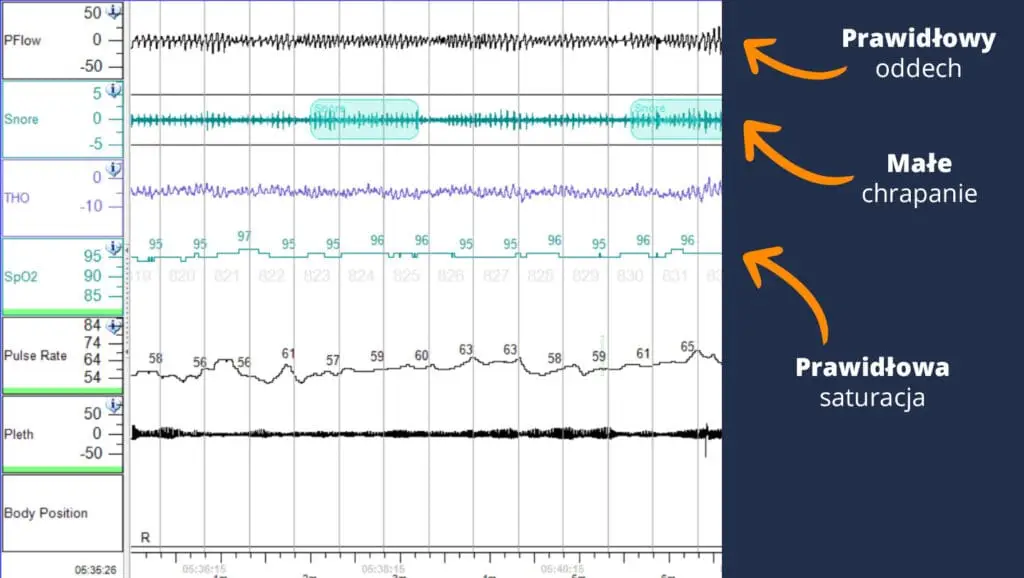

Porównaj te wyniki badania poligrafii snu dwóch różnych chrapiących osób:

Druga osoba chrapie i nie ma bezdechu sennego

W obu przypadkach chrapanie to główny objaw. Ale jest między nimi ogromna różnica!

Drugiemu pacjentowi wystarczła niewielka operacja podniebienia by przestał chrapać.

Natomiast pacjent pierwszy potrzebuje zupełnie innego leczenia.